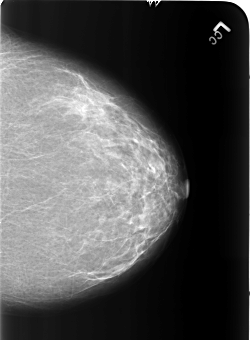

B_3186_1.LEFT_CC

LEFT_CC LINES 5440 PIXELS_PER_LINE 4000 BITS_PER_PIXEL 12 RESOLUTION 50 NON_OVERLAY